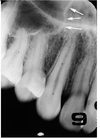

nasal cavities

alar cartilage

This appears more radiolucent than surrounding bone; adjacent to border of nasal bone

canine fossa

inferior border of the mandible

lower lip line

soft tissue of chin; depression from lower lip to superior chin

radiolucent area overlying mandibular incisors

labial depression

This allows for passage of arteries branching from sublingual artery

lingual foramen